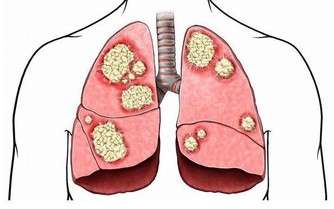

血液粘度、濃度、聚集性和凝固性的異常增高或增強,也是腦梗形成的發病因素之一,對於患有三高的患者,更要格外重視這一點。